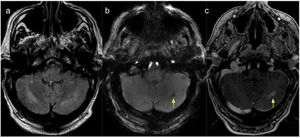

MRI scan of the cerebellum. (A) T2-weighted FLAIR sequence showing hyperintense lesions in the cerebellar hemispheres (dentate nuclei), predominantly on the right side, coinciding with areas of diffusion restriction on DWI sequences (image not displayed). (B) SWAN sequence showing a haemorrhagic focus in the left cerebellum. (C) Contrast T1-weighted sequence revealing foci of increased contrast uptake in the left cerebellum.

A CT scan revealed no alterations; however, as neurological symptoms persisted at 10 days after admission, he underwent a brain MRI scan, which revealed hyperintensities on T2-weighted sequences in both cerebellar hemispheres (dentate nuclei), particularly on the right side, with restricted diffusion on DWI sequences. We also observed a hyperintense focus in the left corona radiata, with diffusion restriction on diffusion sequences and a small area of blood deposition in the left cerebellar hemisphere. Post-contrast sequences revealed contrast uptake in the cerebellar lesions and globi pallidi (Figs. 1 and 2).

These findings are compatible with ischaemic and haemorrhagic processes in the context of heat stroke.